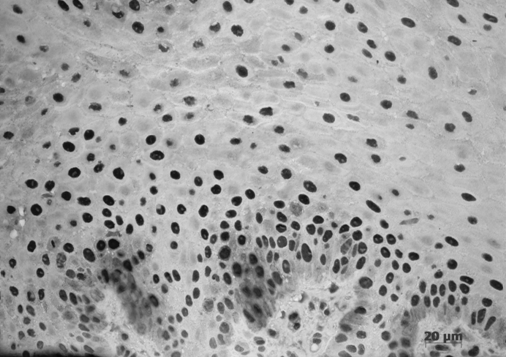

При иммуногистохимическом исследовании тканей десны с хроническим генерализованным пародонтитом легкой степени тяжести выявлялась усиленная пролиферативная активность клеток эпителия. PCNA обнаруживался в ядрах клеток не только базального, но и шиповатого слоев (рис. 3). Следовательно, повышение синтетической активности данных клеток в биоптатах больных являлась проявлением компенсаторно-приспособительных механизмов эпителиальной ткани за счет нарушения микроциркуляции стромы. Митотический индекс эпителиоцитов (PCNA) может свидетельствовать о состоянии барьерной функции десны. Гипертрофия росткового слоя эпителия служит показателем степени тяжести воспалительного процесса, вызванного микробными агентами.

Рис. 3. Хронический генерализованный пародонтит легкой степени. Экспрессия PCNA клетками базального и шиповатого слоев эпителия десны. Иммуногистохимическая реакция на PCNA. Докраска гематоксилином.